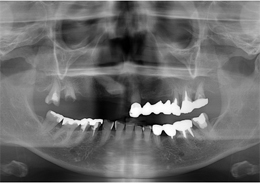

- 治療内容

- 上顎右側に残っていた歯の根及び上顎左側に残存していたが、歯周病により動揺があった歯の抜歯を行い、合計6本のインプラントの埋入を行い、ネジ固定式の上部構造を装着した

- 治療費用

- 上顎ALL-ON-4:4,000,000円(税別)

- 治療期間

- 6ヶ月